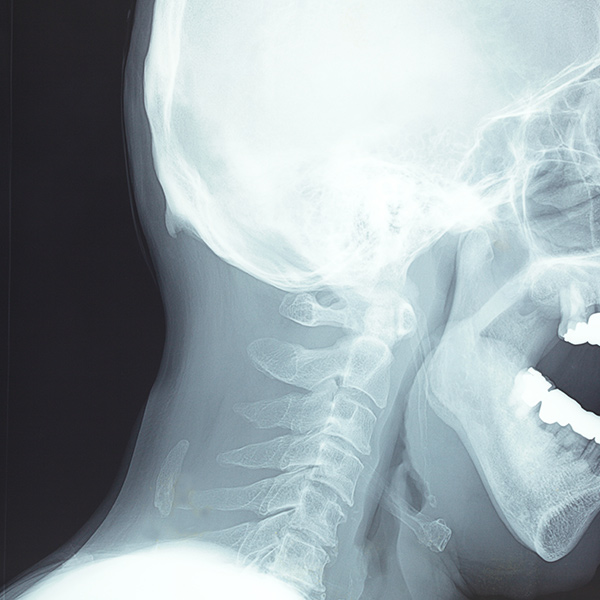

首の骨は、頸椎(けいつい)といいます。首の骨には、頭を支える役割と、頸髄(けいずい)という呼吸や手足を動かすなどの重要な神経を保護する役割があります。首の骨の周りには多くの筋肉があり、それらの筋肉を使うことで頭を動かしたり、頭の位置を保ったりしています。

首の骨の動きを支えるクッションのような大切な役割をしているのが、椎間板(ついかんばん)です。椎間板は、加齢によって痛んだり、変形したりします。

また、首の骨そのものが変形して一部が棘(とげ)のようになったり、椎間板が出っ張ることによって頸髄を圧迫することがあります。こうした病気が「頸椎椎間板ヘルニア」や「頸椎症」と呼ばれています。神経が圧迫されることで、痛みや痺れ、手足に力が入りにくいなどの症状が起こってしまうのです。「肩こり」も、このようにして起こる場合があります。

レントゲンで骨の状態を確認し、病気や症状に合わせた治療(内服液や注射など)とリハビリテーション(運動療法)、温熱や電気治療(物理療法)などを併用した治療をします。